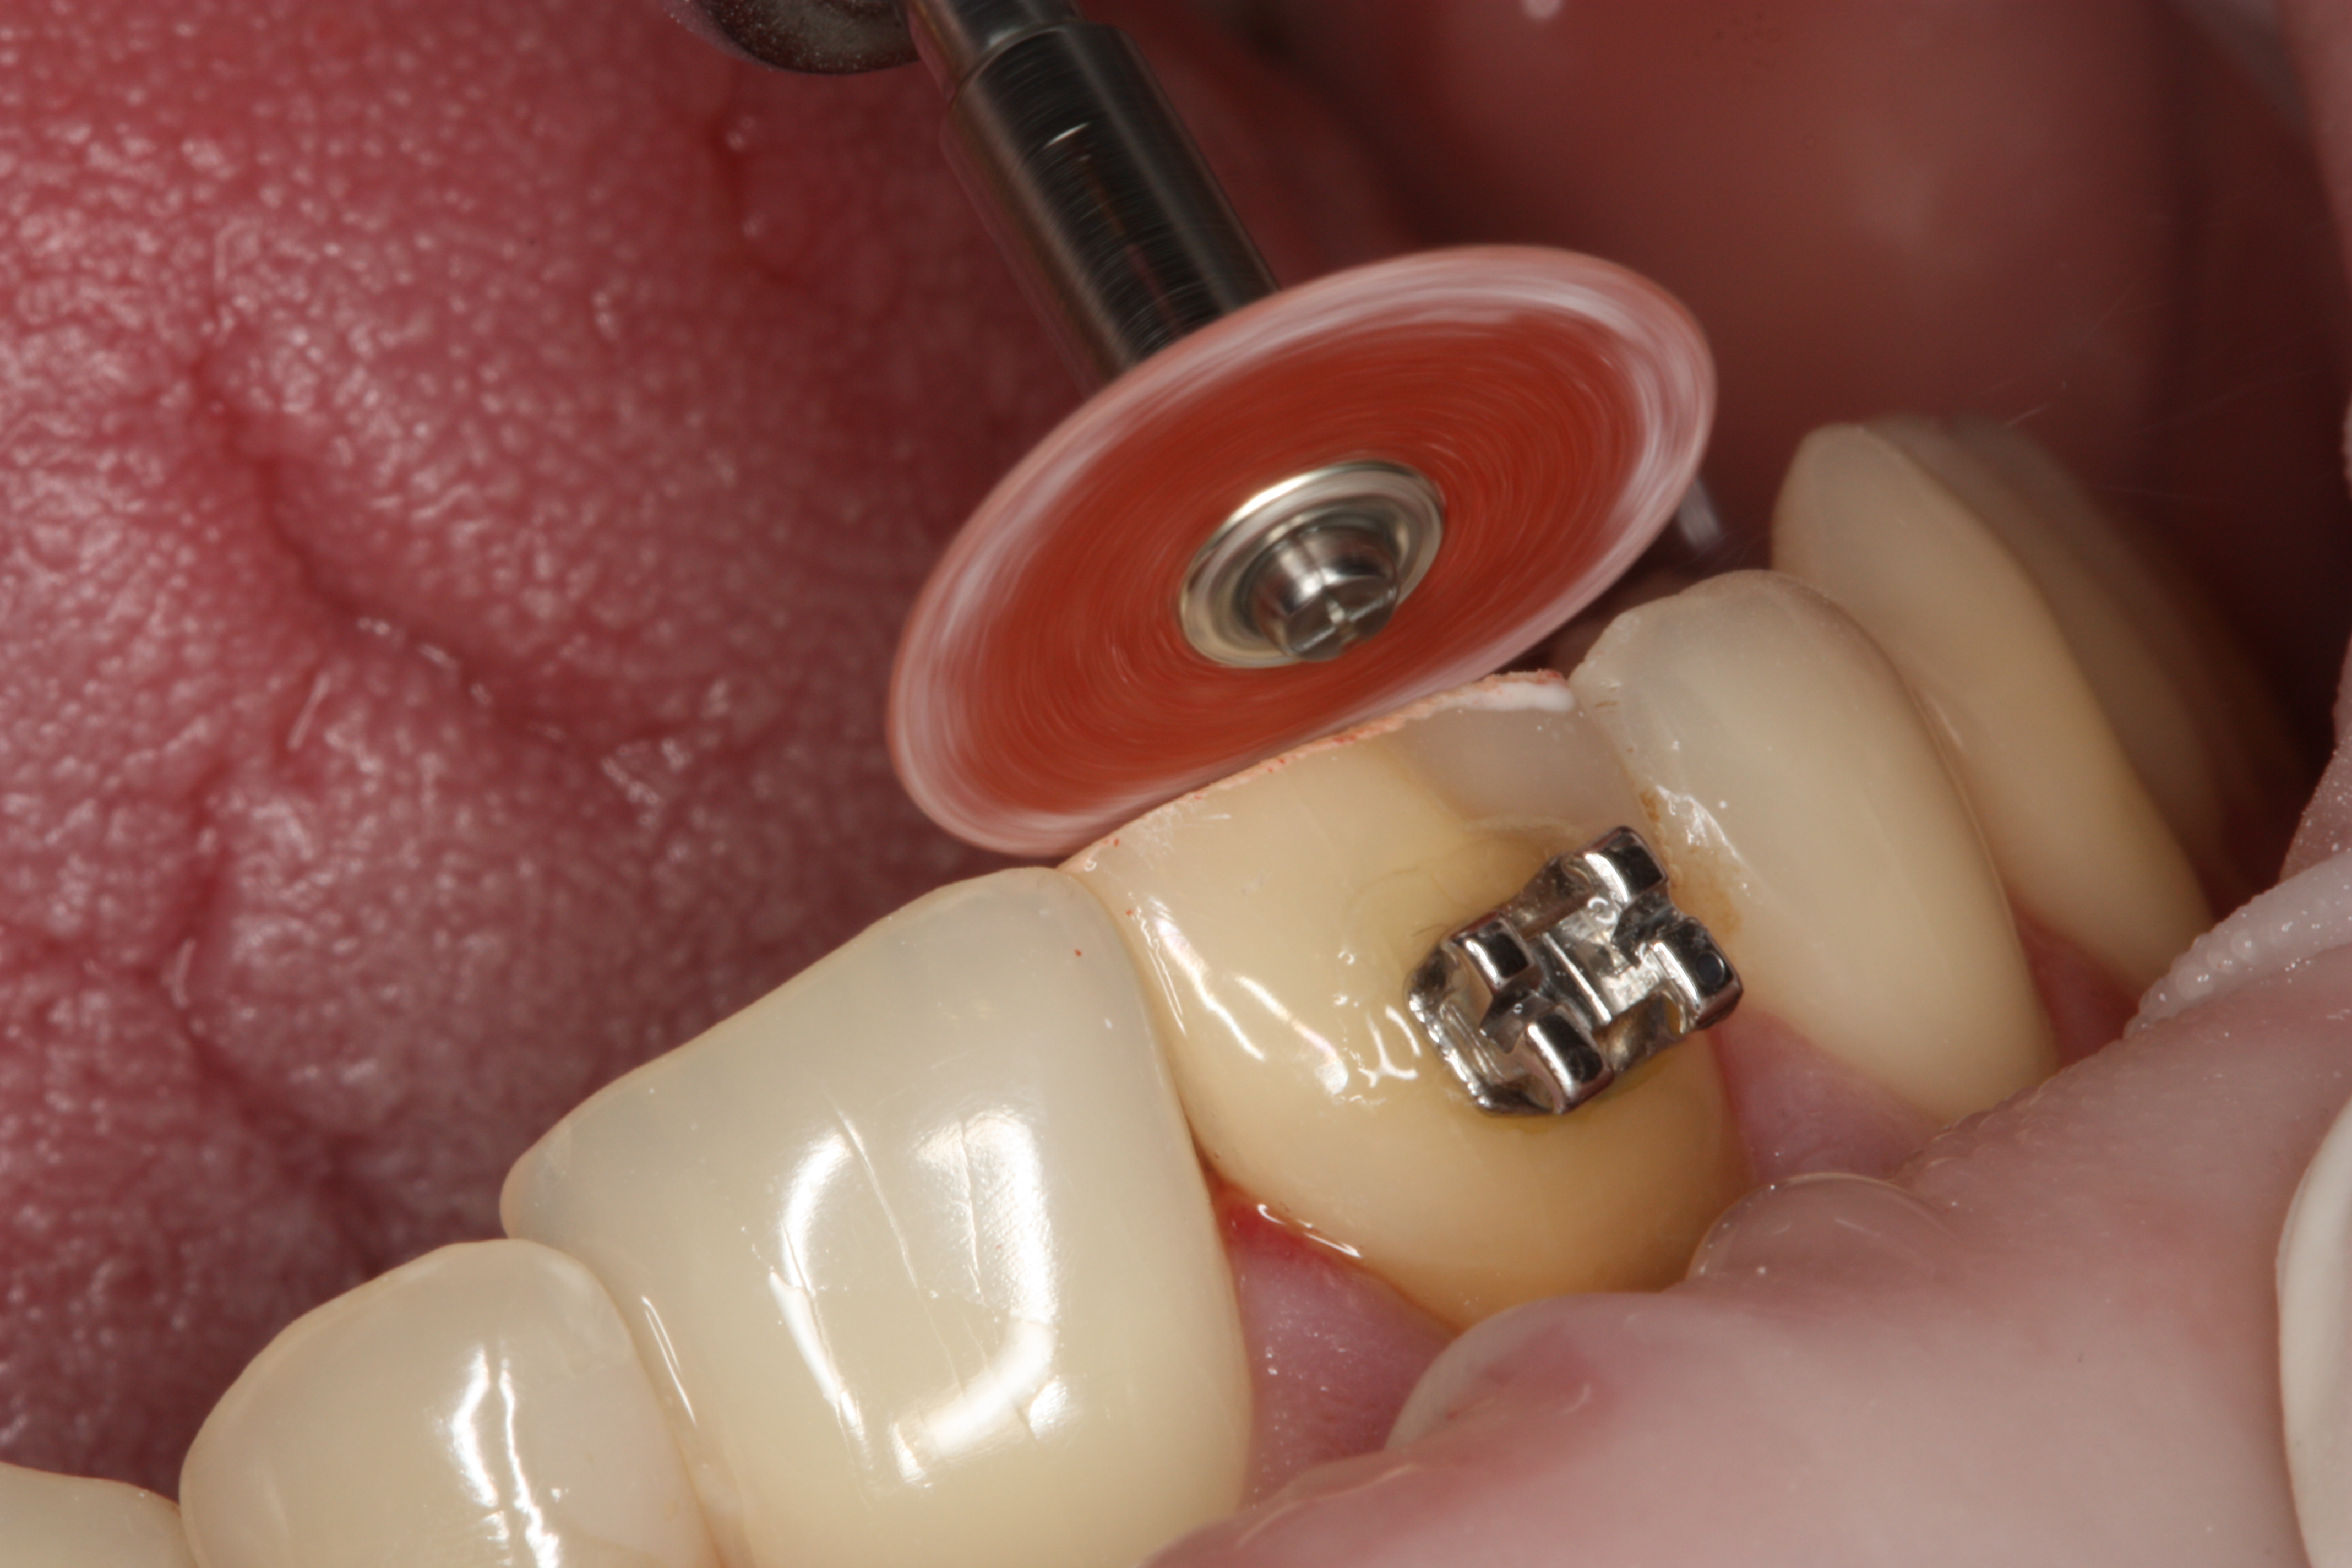

Przykład ekstruzji ortodontycznej za pomocą płytki termoformowalnej i zameczka ortodontycznego: